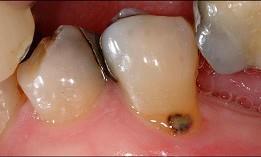

问题 导致老年人龋病发病率升高的原因是 ( )

选项 A.唾液分泌量减少 B.致龋菌的种类改变 C.牙脆性增加 D.食糖量增加 E.牙根外露,根面龋发病率升高

答案 E